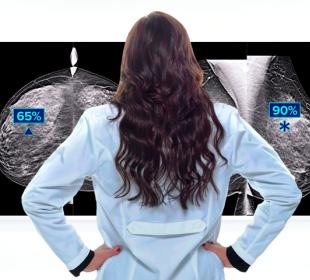

Hologic is transforming breast care. We apply cutting-edge science to accelerate discovery, improve efficiency and continually sharpen precision.

Time is precious when it comes to effective detection, diagnosis and treatment of breast cancer. We strive to save you time at every step along the Continuum of Care.